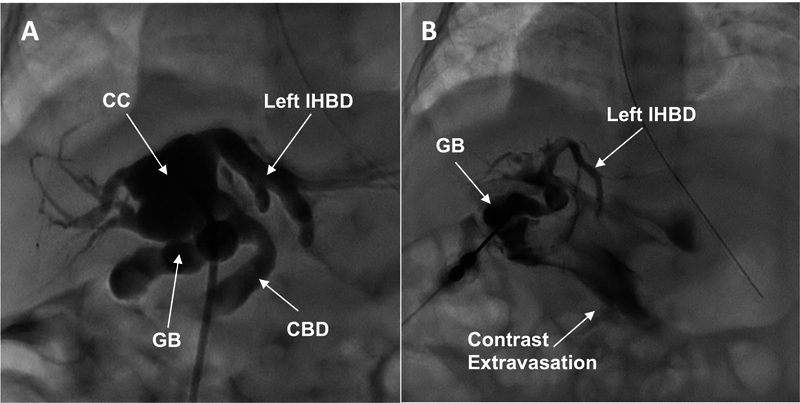

Patients with congenital diaphragmatic hernia (CDH) can present with other congenital anomalies, but an associated choledochal cyst (CC) has rarely been described. The simultaneous diagnosis of both anomalies complicates patient management. There is no consensus on the ideal timing for CC excision. Unrepaired CC is associated with risks of developing biliary sludge, choledocholithiasis, and cholangitis. After a CDH repair with mesh, secondary bacterial translocation caused by a delayed CC repair could lead to mesh superinfection. Conversely, early CC surgical management could cause mesh displacement and lead to CDH recurrence, requiring reintervention. We present the rare case of a CC occurring in a neonate with a prenatally diagnosed right CDH. One month after an uncomplicated CDH repair with mesh, while the patient was still hospitalized for pulmonary hypertension, she developed progressive cholestasis and acholic stools. Investigations revealed a nonpreviously suspected CC. Conservative treatment was attempted, but CC perforation with secondary biliary peritonitis occurred. Open CC excision with a Roux-en-Y hepaticojejunostomy was therefore performed on day of life (DOL) 41. Having suffered no short-term surgical complications, the patient was discharged on DOL 83 because of prolonged ventilatory support due to pulmonary hypertension. Now 12 months after surgery, she is doing well with normal liver function tests and imaging studies. In summary, CC should be considered in the differential diagnosis of progressive cholestasis in patients with CDH. Surgical repair of a symptomatic CC should not be delayed even in the presence of mesh given the risks of CC complications.

先天性膈疝(CDH)患者可能伴有其他先天性畸形,但伴有胆总管囊肿(CC)的病例却很少见。同时诊断出这两种畸形会使患者的治疗变得复杂。关于切除 CC 的理想时机,目前还没有达成共识。未修复的CC有发展成胆汁淤积、胆总管结石和胆管炎的风险。在使用网片进行CDH修复后,延迟CC修复引起的继发性细菌易位可能导致网片超级感染。反之,过早进行CC手术治疗可能会导致网片移位,导致CDH复发,需要重新进行手术治疗。我们介绍了一例产前确诊为右侧 CDH 的新生儿发生 CC 的罕见病例。在使用网片进行无并发症的CDH修补术一个月后,患者因肺动脉高压仍在住院治疗,但出现了进行性胆汁淤积和大便隐痛。检查结果显示她患有之前未被怀疑的CC。医生尝试了保守治疗,但还是发生了CC穿孔和继发性胆道腹膜炎。因此,患者在生命第41天(DOL)进行了开放式CC切除术和Roux-en-Y肝空肠吻合术。患者没有出现短期手术并发症,但由于肺动脉高压而需要长时间的呼吸支持,因此于第 83 天出院。术后 12 个月,她的肝功能检查和影像学检查均正常。总之,CDH 患者进行性胆汁淤积的鉴别诊断中应考虑到 CC。鉴于CC并发症的风险,即使存在网片,也不应延迟对有症状的CC进行手术修复。